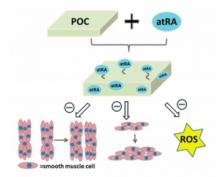

CHIRURGIE et PLAIES VASCULAIRES: Un matériau biodégradable pour une juste cicatrisation